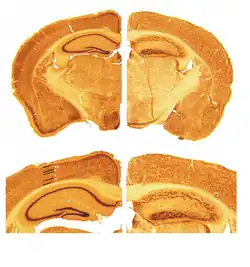

Reelin's name comes from the abnormal reeling gait of reeler mice,[17] which were later found to have a deficiency of this brain protein and were homozygous for mutation of the RELN gene. The primary phenotype associated with loss of reelin function is a failure of neuronal positioning throughout the developing central nervous system (CNS). The mice heterozygous for the reelin gene, while having little neuroanatomical defects, display the endophenotypic traits linked to psychotic disorders.[18]

The "reeler" mouse was described for the first time in 1951 by D.S.Falconer in Edinburgh University as a spontaneous variant arising in a colony of at least mildly inbred snowy-white bellied mice stock in 1948.[17] Histopathological studies in the 1960s revealed that the cerebellum of reeler mice is dramatically decreased in size while the normal laminar organization found in several brain regions is disrupted.[19] The 1970s brought about the discovery of cellular layer inversion in the mouse neocortex,[20] which attracted more attention to the reeler mutation.

Mammalian corticogenesis is another process where reelin plays a major role. In this process the temporary layer called preplate is split into the marginal zone on the top and subplate below, and the space between them is populated by neuronal layers in the inside-out pattern. Such an arrangement, where the newly created neurons pass through the settled layers and position themselves one step above, is a distinguishing feature of mammalian brain, in contrast to the evolutionary older reptile cortex, in which layers are positioned in an "outside-in" fashion. When reelin is absent, like in the mutant reeler mouse, the order of cortical layering becomes roughly inverted, with younger neurons finding themselves to be unable to pass the settled layers. Subplate neurons fail to stop and invade the upper most layer, creating the so-called superplate in which they mix with Cajal-Retzius cells and some cells normally destined for the second layer.